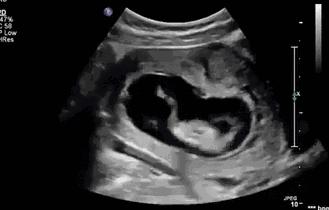

其实小家伙很小的时候就已经开始“闹腾”了:妥妥的一个运动健将!

小碎步向前缩,撅着小屁股用力一蹬,身体向后滑去——“母胎版蛙泳”动作很标准嘛!

▼

不行,刚才的动作不够标准,再来一次!

不过,力气好像还是太小了,算了,休息休息再说~